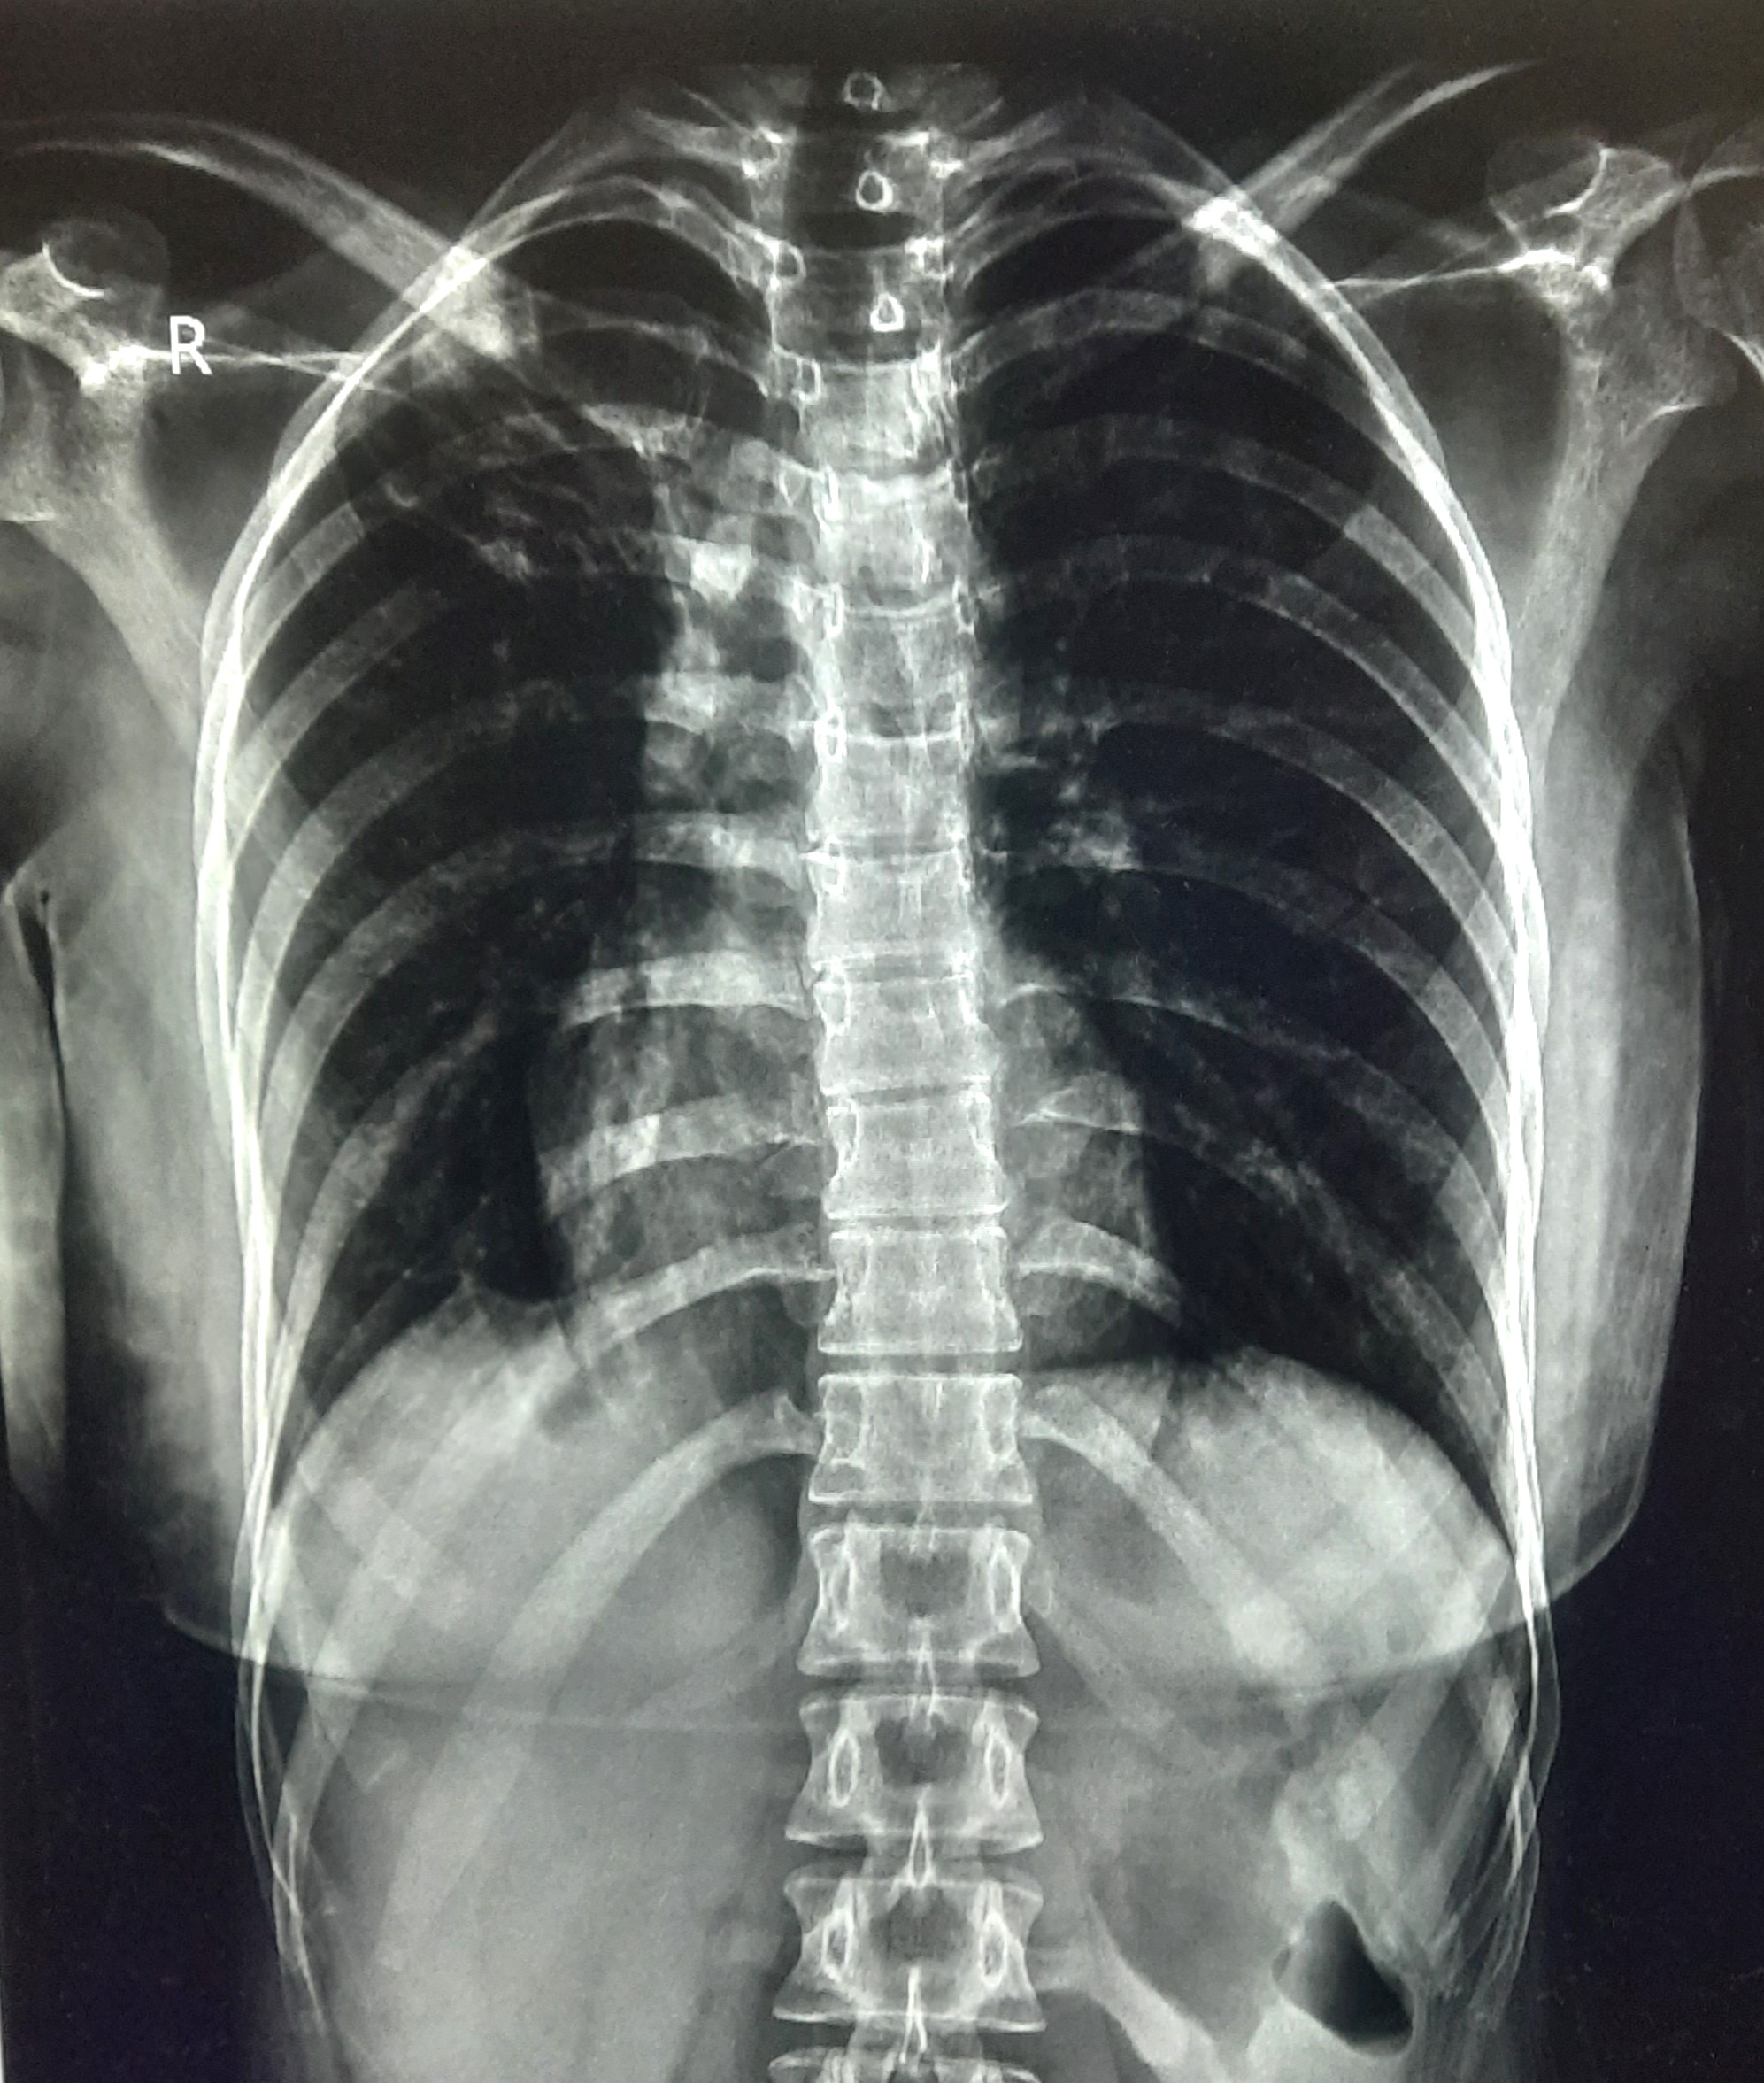

| 53 | IGGMC, Nagpur, Nagpur | P2 | 29-4419 | Rasul Ali | Consent taken on Paper | 36 Yrs. |

Provisional Diag : ?

Final Diag : COPD |

Non-TB Case (Confirmed) | Prominence of broncho vascular markings in bilateral Mid zone il Defined Non-Homogenous Lesion, Changes Of COPD | Abnormality visible on x-ray |